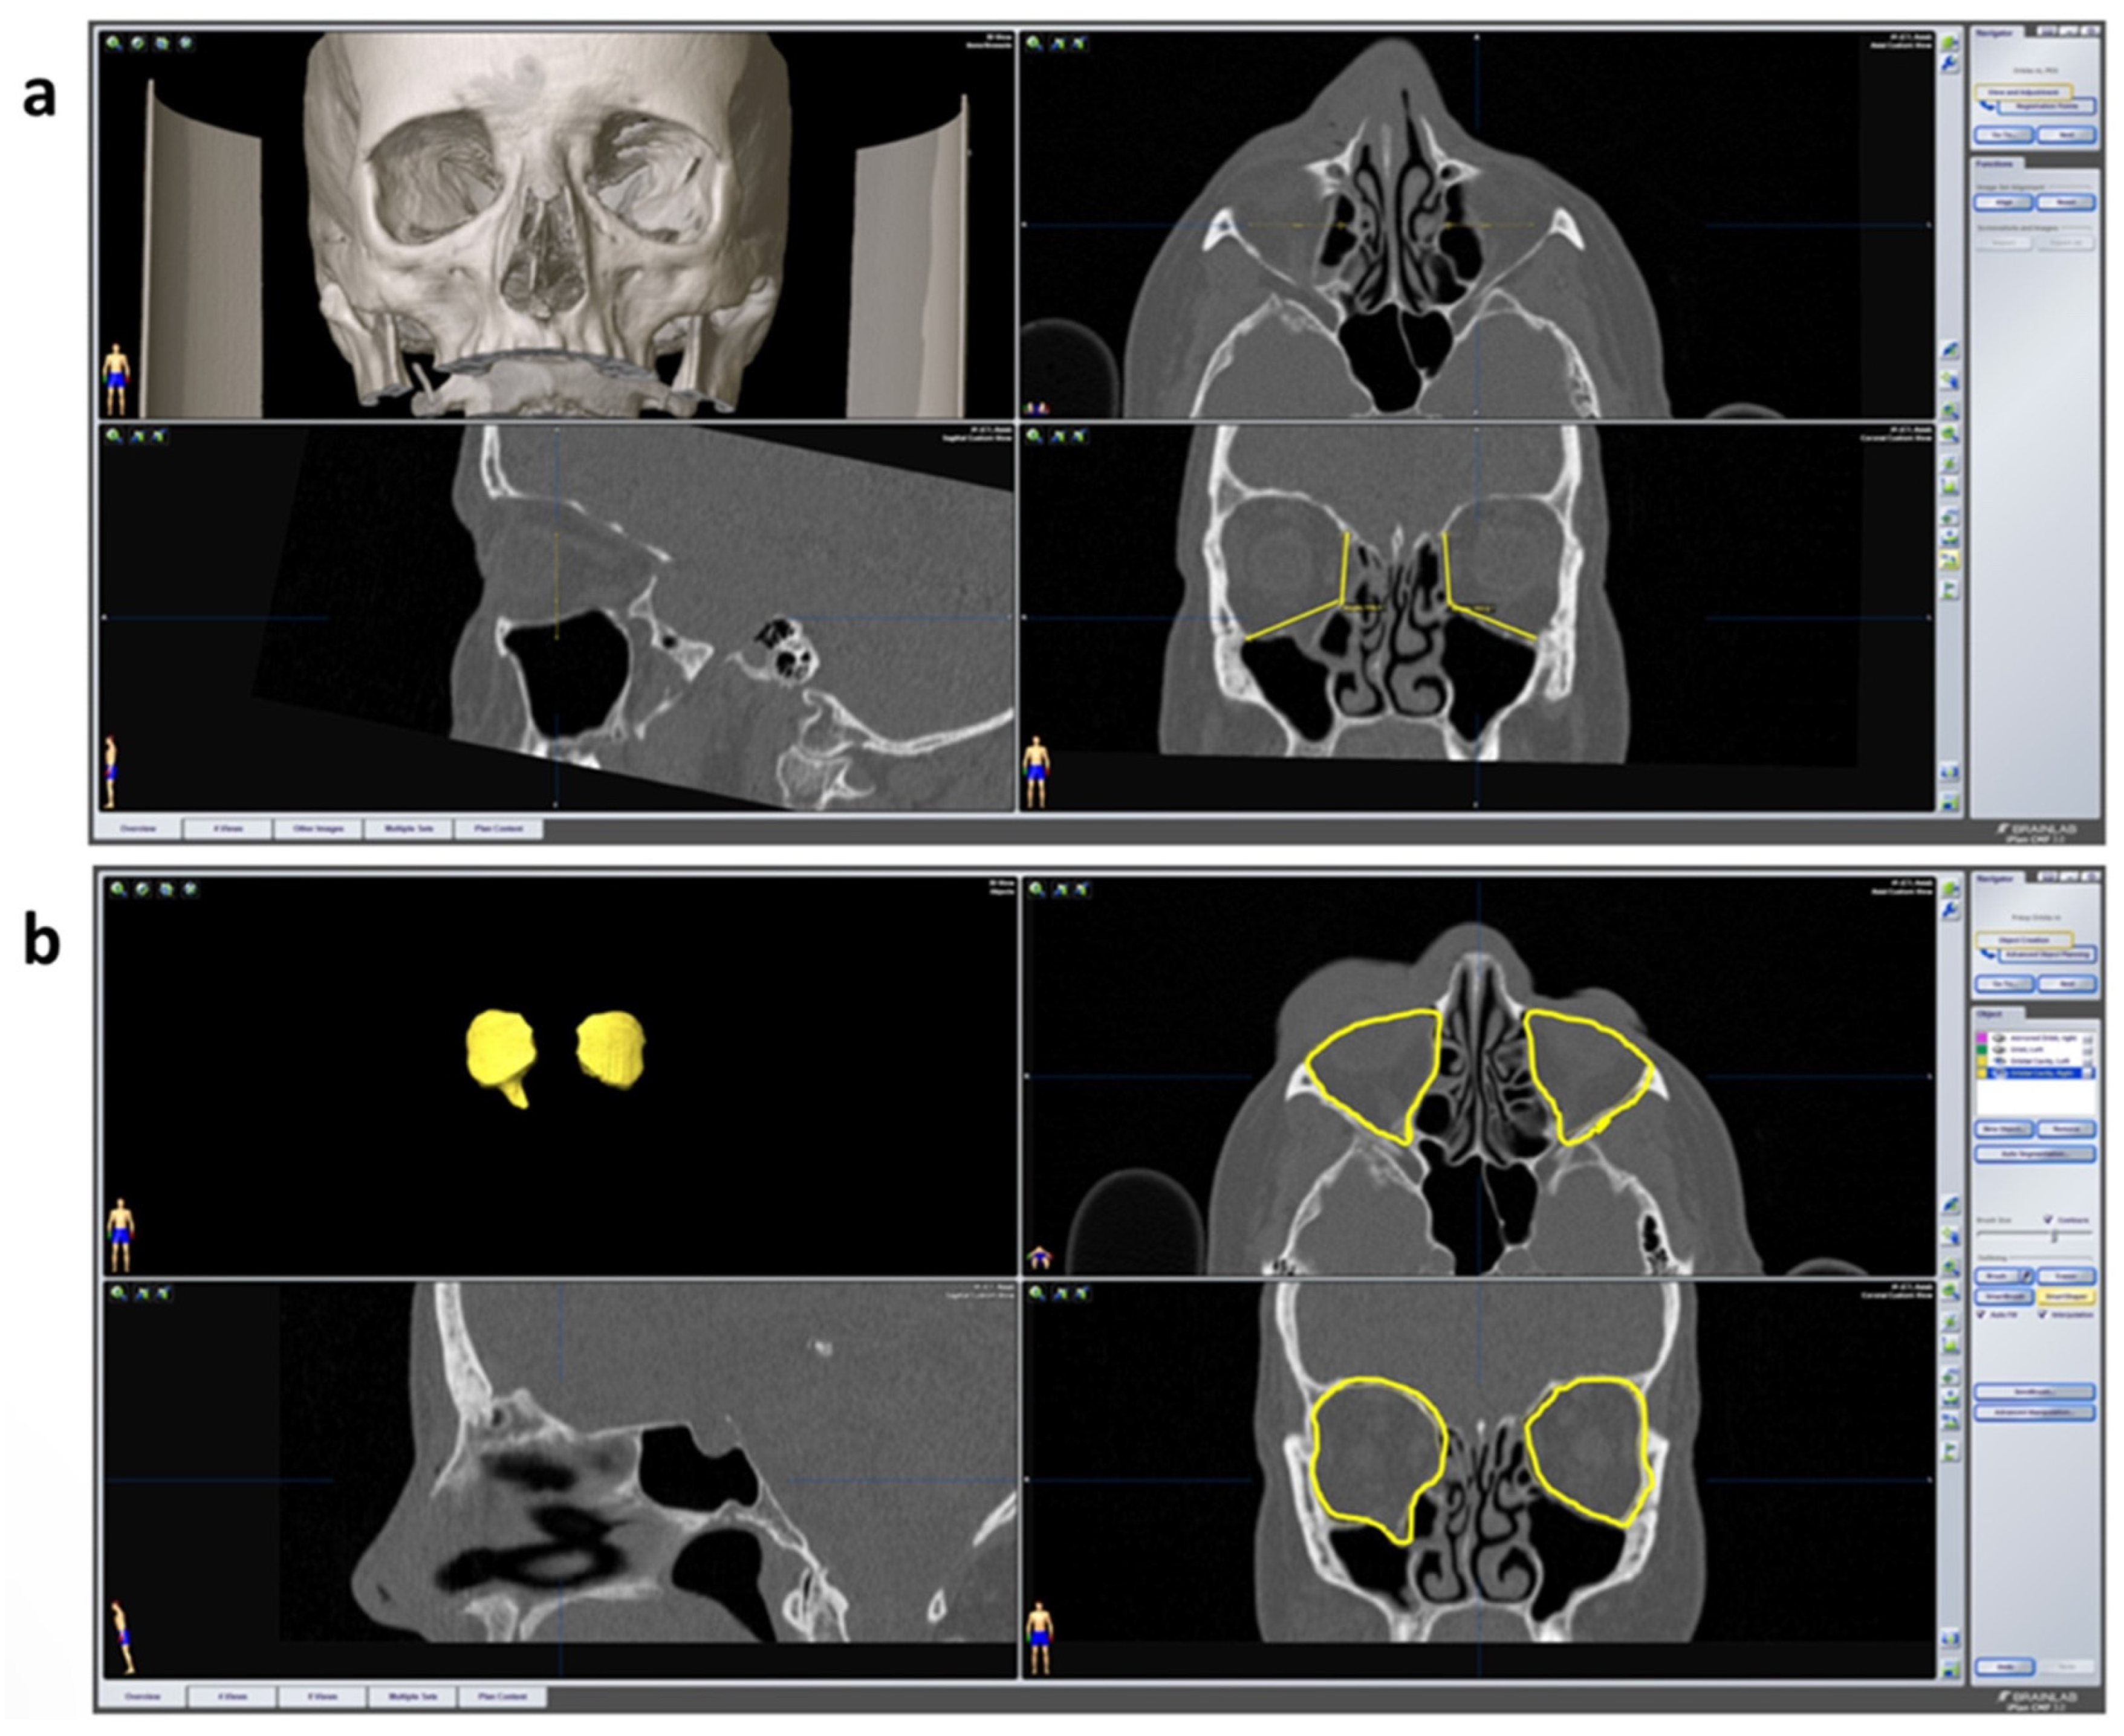

For the healthy and the fractured orbit, respectively, an angle measurement was carried out between the medial orbital wall and the orbital floor in the coronary plane with the following three defined points: the cranial boundary of the medial wall, the transition zone and the transition of the orbital floor to the lateral wall (see Figure 4a). The measurement was carried out for both sides in the anterior, middle and posterior thirds of the orbit. These were defined in the sagittal plane by the anterior bony orbital margin, the posterior bony boundary (the so-called “posterior ledge”) and the middle of this route.

Figure 4.

Radiological parameters. (a) Angle measurement between the medial orbital wall in iPlan CMF 3.0.5. in coronary layer. The datasets are shown in multi-planar view including 3D reconstruction, axial, sagittal and coronary plane. At the bottom right, the angles of both orbits can be seen in yellow. The values are automatically calculated by the program and displayed. (b) Orbital cavity algorithm for automatic volume calculation in iPlan CMF 3.0.5. At the top left the segmented orbital cavities are displayed in 3D volume. On the upper right (axial) and bottom right (coronary), the outlines of the orbits are shown in yellow created via the “smart shaper” function. The right orbital content herniates into the maxillary cavity (“drop-shape”) due to the fracture of the orbital floor.

For volume measurement of the healthy and fractured side, both orbital cavities were segmented by the program after selection via the menu item “object creation” (see Figure 4b). The outlines of the enlarged volume of the fractured side were dragged manually via the “smart shaper” option to define the volumes individually.